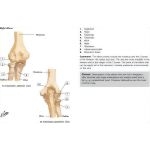

Bones of Elbow

Bones of Elbow

Labeled - Cleland Ortho Clinical Exam 1E